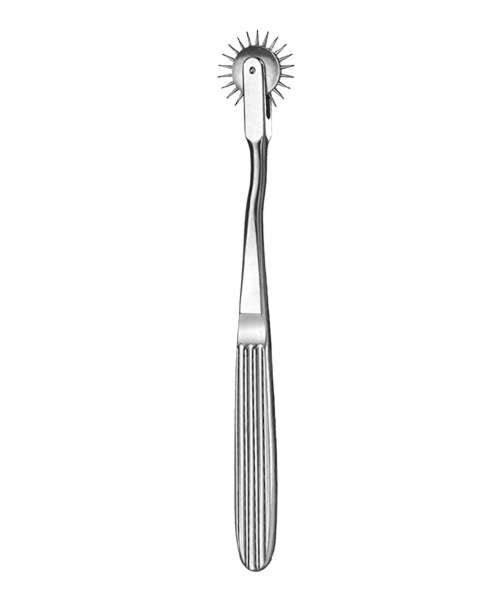

- Diagnostics, Surgical Instruments

Pinwheel

- Size : 21 CM - 8 1/4"